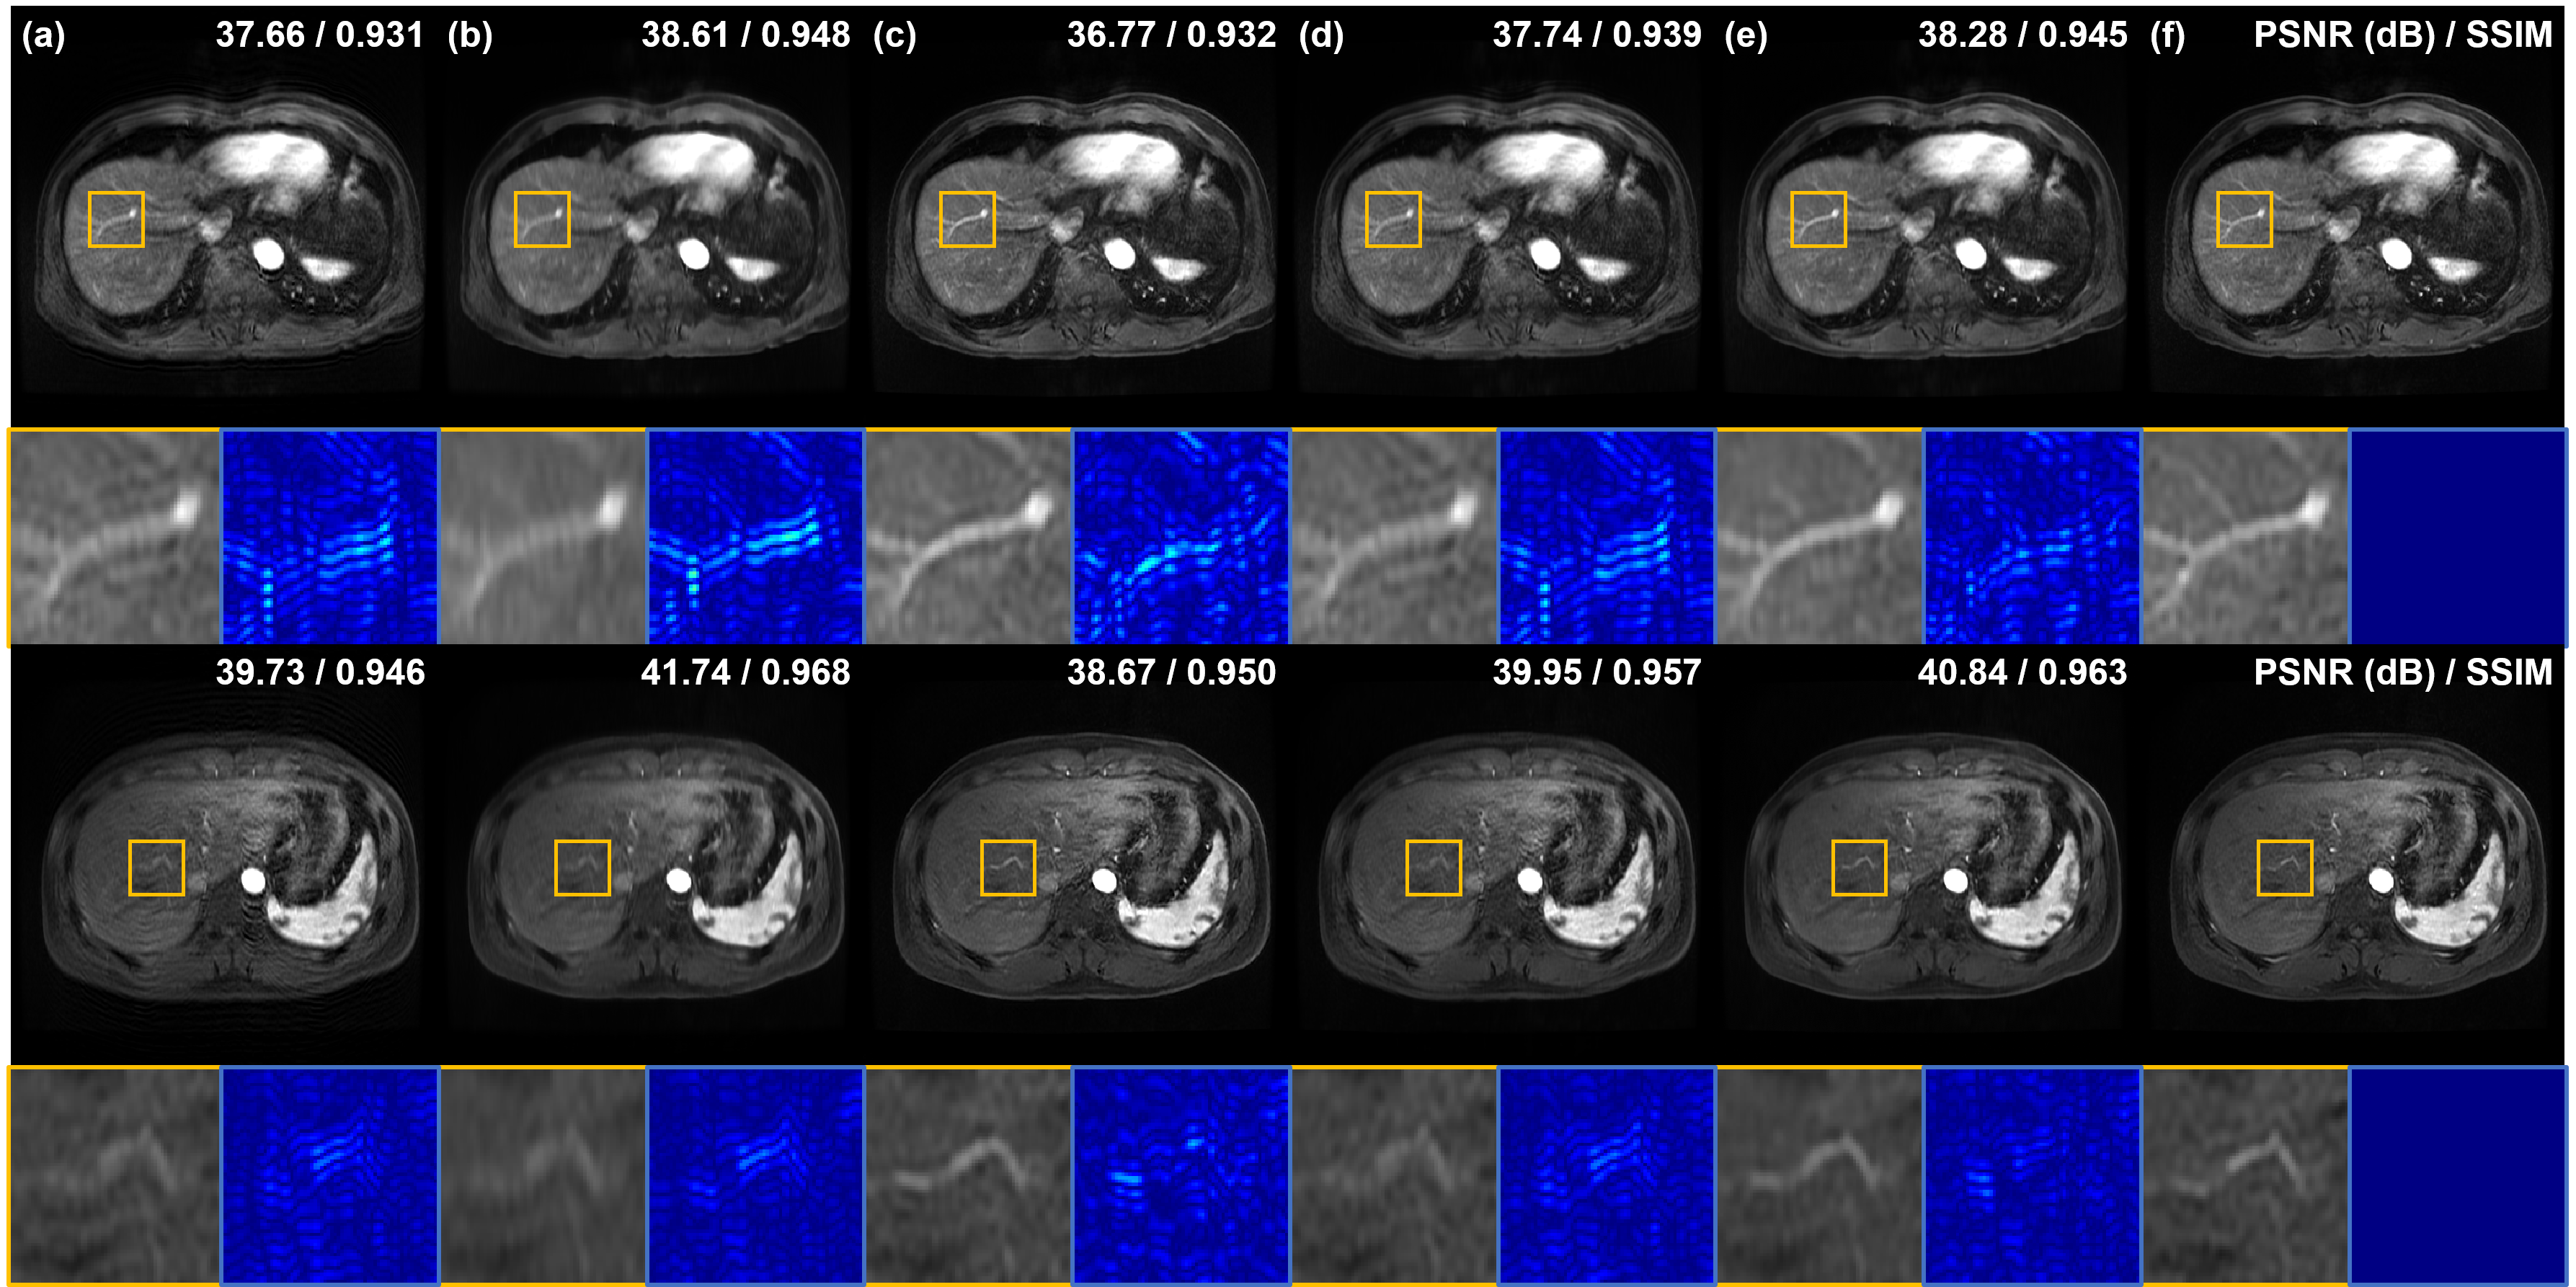

Fig. 3 shows the motion artifact reduction results of various methods with random simulated motion-corrupted data. As shown in Fig. 3(a), it is hard to recognize detailed structures of brains due to motion artifacts. MARC [16] reduces the motion artifact but the output images of MARC are too blurry or smoothed (Fig. 3(b)). In the results of MARC, the boundary between gray matter and white matter is not clear (the first row in Fig. 3(b)), and the structure of the choroid plexus is not properly restored (the second row in Fig. 3(b)). Next, in Fig. 3(c) and (d), Cycle-MedGAN V2.0 [20] and bootstrap subsampling and aggregation [23] remove random motion artifacts significantly and show increased quantitative results compared to input images. However, there are some differences between label images and outputs of Cycle-MedGAN V2.0 as shown in difference maps, and bootstrap subsampling and aggregation [23] shows blurrier edge details compared to label images. On the other hand, as shown in Fig. 3(e), the proposed method shows the best qualitative and quantitative results among all methods. Especially, the proposed method shows the sharpest boundary between gray and white matters among methods as shown in the first row of Fig. 3.

Next, we compare motion artifact reduction methods using simulated respiratory motion-corruption data. In Fig. 4(a), the vasculature of the liver is damaged or blurred due to motion artifacts. Especially, artifacts appear most severe around blood vessels. MARC removes motion artifacts and achieves high quantitative metric values, but the blood vessels still look blurry as shown in Fig. 4(b). On the other hand, Cycle-MedGAN V2.0 [20] sharp reconstructed results but the PSNR of results of Cycle-MedGAN V2.0 is lower than that of input images (4(c)). It is maybe because Cycle-MedGAN V2.0 changes image intensity or details. Results of bootstrap subsampling and aggregation [23] are shown in Fig. 4(d), resulting in images with reduced motion artifacts and improved quantitative metrics compared to input images. However, some motion artifacts near the blood vessels remain (the first row of Fig. 4(d)), and it is hard to recognize the vessel due to blurring and remaining artifacts (the second row of Fig. 4(d)). Meanwhile, the proposed method shows the most similar restoration results to the label images as shown in Fig. 4(e) and (f). Specifically, the vascular structure is most clearly and accurately restored by the proposed method. Furthermore, our method significantly reduces motion artifacts around the blood vessels compared to other methods.